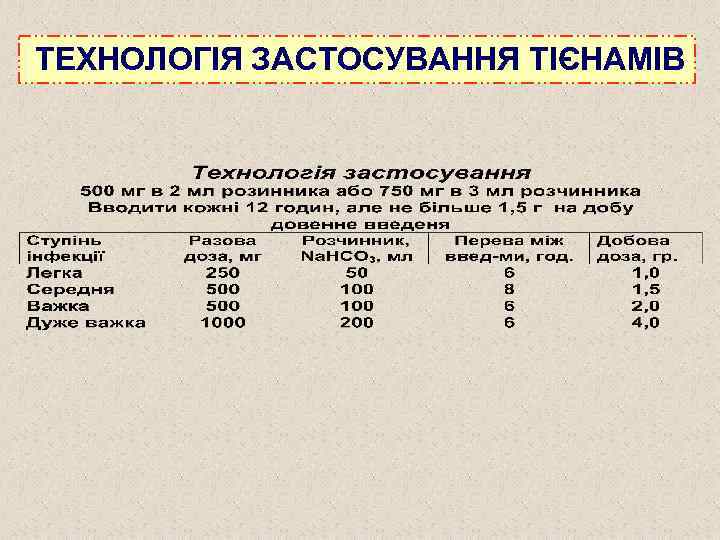

ТЕХНОЛОГІЯ ЗАСТОСУВАННЯ ТІЄНАМІВ